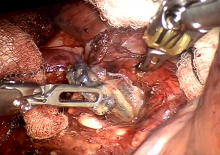

This video demonstrates a robotic right upper lobectomy, performed using the Cerfolio method of port placement. All vessel and pulmonary divisions were performed using the Signia™ powered stapler (Medtronic, Dublin, Ireland), with the use of a leader catheter on the majority of occasions.